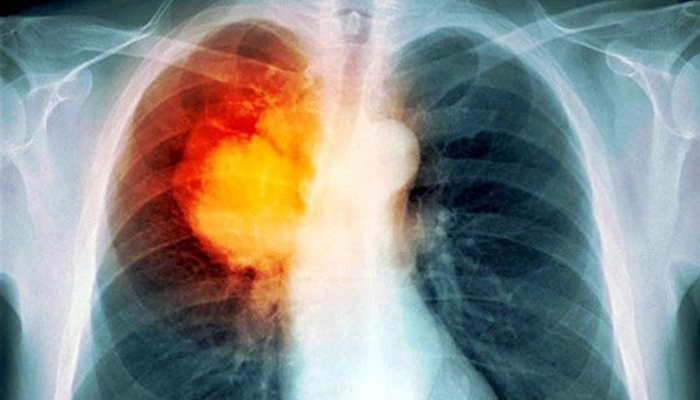

Tái phát lao phổi có thể do thất bại điều trị, tái hoạt nội sinh hoặc tái nhiễm ngoại sinh